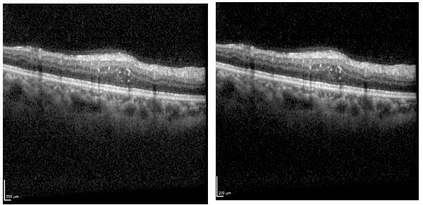

Ophthalmic diseases represent a significant global health issue, necessitating the use of advanced precise diagnostic tools. Optical Coherence Tomography (OCT) imagery which offers high-resolution cross-sectional images of the retina has become a pivotal imaging modality in ophthalmology. Traditionally physicians have manually detected various diseases and biomarkers from such diagnostic imagery. In recent times, deep learning techniques have been extensively used for medical diagnostic tasks enabling fast and precise diagnosis. This paper presents a novel approach for ophthalmic biomarker detection using an ensemble of Convolutional Neural Network (CNN) and Vision Transformer. While CNNs are good for feature extraction within the local context of the image, transformers are known for their ability to extract features from the global context of the image. Using an ensemble of both techniques allows us to harness the best of both worlds. Our method has been implemented on the OLIVES dataset to detect 6 major biomarkers from the OCT images and shows significant improvement of the macro averaged F1 score on the dataset.